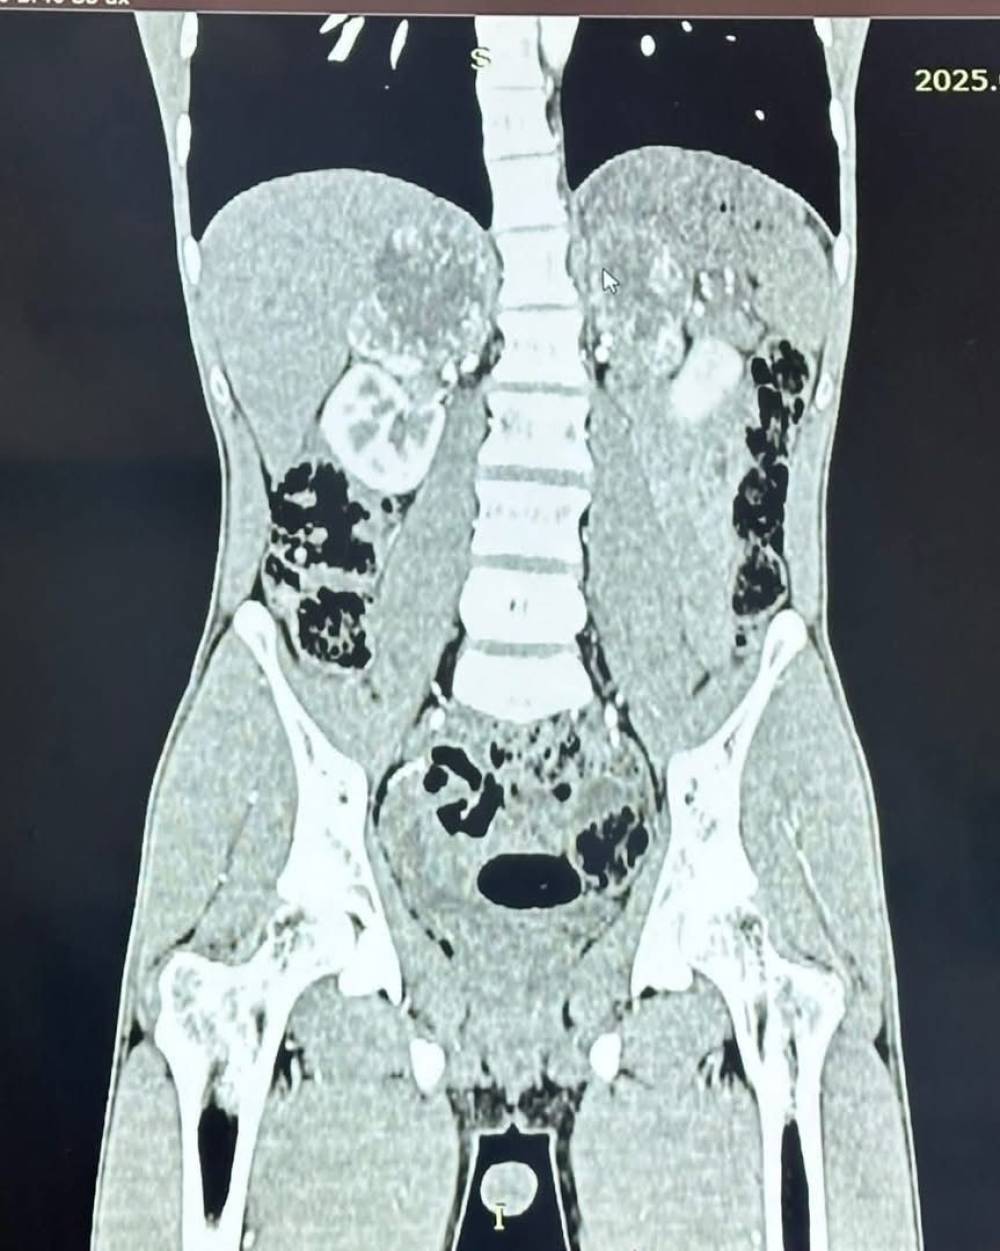

فريق طبي بجامعة البصرة ينجح في استئصال غدتين كظريتين...